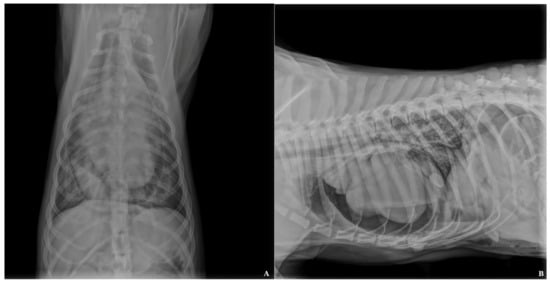

2.2. Diagnostic Imaging